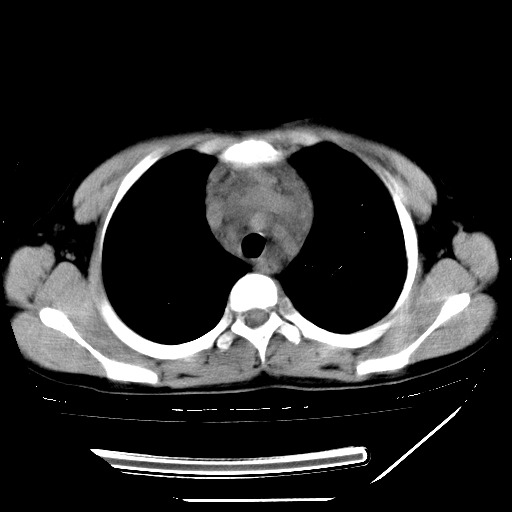

男,13岁,咳嗽、咳痰伴发热一周。

上纵隔课件多枚淋巴结,部分相互融合,左侧支气管壁增厚,肺纹理较右侧增粗,患者,男,13岁,

中上纵隔见多枚淋巴结肿大,部分相互融合成团片,左肺门增大,上叶支气管变窄,肺内多处斑片状 索条状及棉絮状致密影。临床“男,13岁,咳嗽、咳痰伴发热一周。”首先考虑:原发综合征!不除外淋巴瘤可能!

纵隔多发肿大淋巴结,部份有融合改变。双肺血管气管束增厚,以肺门为中心向外周散发,以左肺下叶为明显。考虑淋巴瘤可能性大。不除外原发综合征。

中上纵隔见多枚淋巴结肿大,部分相互融合成团片,左肺门增大,上叶支气管变窄,左肺支气管血管束增粗,可见磨玻璃样影。临床“男,13岁,咳嗽、咳痰伴发热一周。”首先考虑:淋巴瘤可能性大!